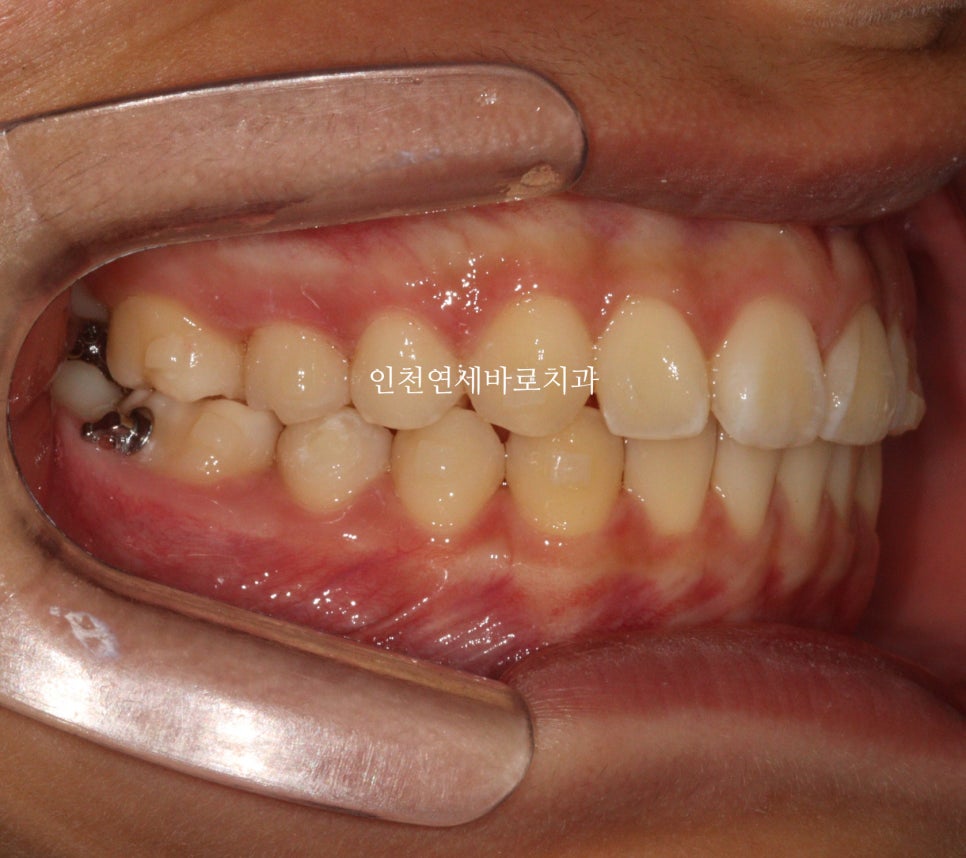

2024년 중간 경과

중간 모습입니다.

공간을 살살 벌리니 위에 위치하고 있던 치아사 살살 내려옵니다.